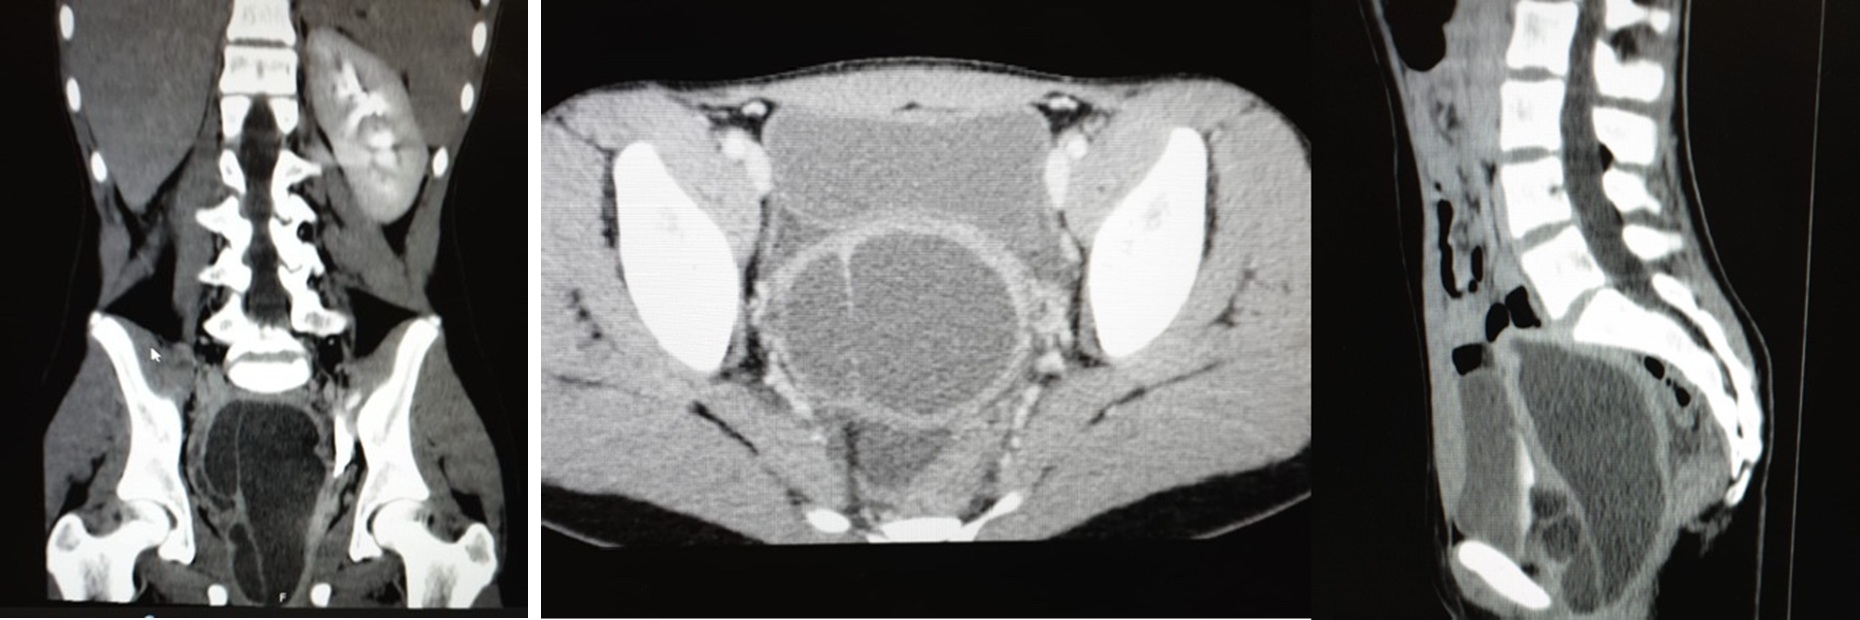

A 12-year-old girl, with an irrelevant medical history, was admitted to the pediatric emergency department with pollakiuria and abdominal and genital pain for two weeks, with worsening in the day before admission. There was a reference to menarche in the six months before, with scarce catamenia and intense dysmenorrhea refractory to NSAIDs. Last catamenia had been two weeks prior to the admission. On physical examination, the lower abdominal quadrants were rigid and painful on palpation and decompression, mainly in the right iliac fossa. An analytical study, urinalysis and pregnancy test were performed, all negative. Therefore, she did an abdominal ultrasound which suggested an hematocolpus (Fig. 1), but could not correctly evaluate the uterus. To better characterization, an abdominal and pelvic computized tomography was carried out which revealed the absence of the right kidney and retroaortic left renal vein, duplication of the uterus, cervix, and vagina, and marked distension of the right hemivagina and endometrial cavity, with hematocolpos, suggesting vaginal obstruction (Fig. 2). Afterwards, she did a renal scintigraphy for a renal morphofunctional assessment, which confirmed a right renal agenesis (Fig. 3). These findings allowed the diagnosis of an OHVIRA syndrome.

Figure 2: Abdominal and pelvic computed tomography: right kidney and retroaortic left renal vein agenesis; duplication of the uterus, cervix, and vagina; hematocolpos.